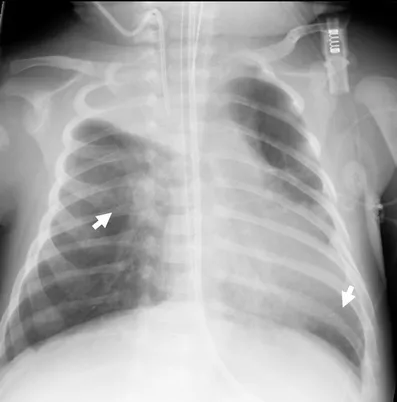

⭐ On frontal neck X-ray, subglottic edema creates the classic "steeple sign."

- Hallmark: Croup (laryngotracheobronchitis) with "steeple sign" on X-ray.

- Croup is identified by its "seal-bark" cough and steeple sign on X-ray.